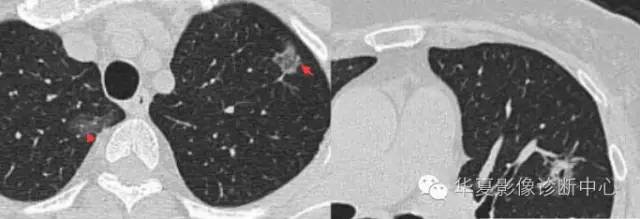

周围GGO边界清楚,分叶征、胸膜凹陷征、含气支气管,混合型GGO

两个病灶

磨玻璃结节良恶性影像分析策略 磨玻璃结节良恶性影像分析策略磨玻璃结节良恶性影像分析策略 其中血管显示清楚,GGO

边界清楚,分叶征,空泡征